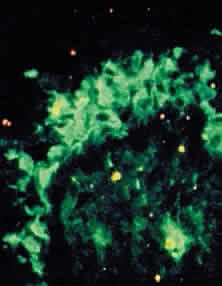

Conjunctival biopsies taken from patients with CP demonstrate immunoglobulins and complement bound to the basement membrane (Fig. 9) 24,37–43 One targeted basement membrane component may be laminin.44 The destruction of laminin, which normally binds basal epithelium to its basement membrane, leads to blister formation.45 An animal model of subepithelial blistering diseases has been developed using antilaminin antibodies in neonatal mice.46 Further damage causes fragmentation of the basement membrane and subsequent repair with aberrant forms of basement membrane collagen.47 Immunoglobulin deposition on the conjunctival basement membrane also may be found in other diseases.24,38,43,48

|